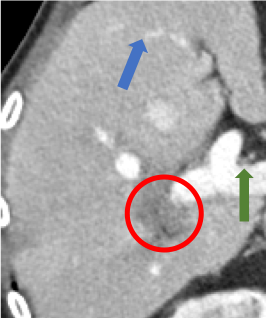

To demonstrate the effectiveness of the proposed network, we perform the qualitative comparisons over three representative abdominal images presented in Figs. 3, 5 and 7. For better evaluations of the image quality with different denoising models, zoomed regions-of-interest (ROIs) are marked by red rectangles and shown in Figs. 4, 6 and 8 respectively. Note that all results from different denoising models focus on two aspects: content restoration and noise-reduction. All CT images in axial view are displayed in the angiography window [-160, 240]HU.

The real NDCT images and corresponding LDCT images are presented in Figs. 3a and 3b. As observed, there are distinctions between ground truth (NDCT) images and LDCT images. Figs. 3a and 7a show the lesions/metastasis. Fig. 5a presents focal fatty sparing/focal fat. In Figs. 4a, 6a and 8a, these lesions can be clearly observed in NDCT images; in contrast, from Figs. 4b, 6b, and 8b, it can be seen that the original LDCT image is noisy, and lacks structural features for task-based clinical diagnosis. All adopted denoising models suppress noise to some extent.

Indeed, the images of WGAN-VGG[37], as shown in Fig. 3j, exhibit better visual quality with respect to more details and share structural details similar to NDCT images according to human perceptual evaluations. However, Figs. 4j (marked by the red circle) and 6j (marked by the green circle) suggest that it may severely distort the original structural information. A possible reason is that the VGG network [47] is a pre-trained deep CNN network based on natural images, and the structural information and contents of natural images are different from medical images.

Compared with WGAN and WGAN-VGG, our proposed SMGAN-3D, as shown in Figs. 4l (marked by the red circle) and 6l (marked by the green circle), can more clearly visualize the metastasis and better preserve of the portal vein.